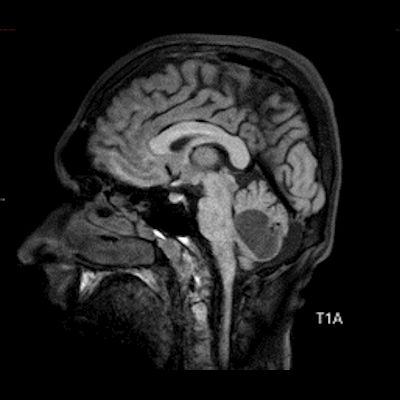

- A) Beyin BT incelemede; posterior fossada hipodens, düzgün sınırlı kistle beraber (oklar), posteriorunda 8 mm boyutunda, iyi sınırlı, kontrastsız BT’de parankim ile izodens, postkontrast görüntülerde yoğun kontrast tutulumu gösteren mural nodül komponenti (oklar) gözlenmektedir.

- B) Beyin MRG incelemesinde; 4. ventriküle bası etkisi oluşturan yaklaşık 3.5 cm boyutta, T2A hiperintens T1A hipointens kistik komponent (oklar) ve posteriorunda T1 ve T2A serilerde parankim ile izointens, içerisinde flow void alanların (oklar) izlendiği, post kontrast görüntülerde yoğun kontrast tutulumu gösteren mural nodül (oklar) barındıran düzgün sınırlı lezyon izlenmektedir.

- BT’de tipik olarak iyi sınırlı, hipodens kistik bir lezyon ve içinde belirgin şekilde kontrastlanan mural nodül izlenir.

- Kontrastlı incelemelerde mural nodül belirgin ve yoğun kontrast tutulumu gösterir. Ancak kist duvarında genellikle kontrastlanma beklenmez.